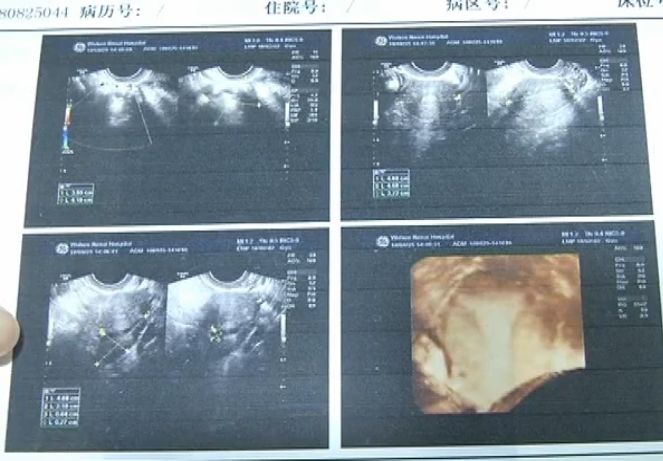

随着年龄增大,小张也到了谈婚论嫁的年纪了,婚期就定在今年底。考虑到婚后要怀孕生小孩,于是,前两天,小张在男友的陪伴下来到武汉做体检。结果B超显示,小张的左侧卵巢呈多囊样改变,右侧附件区有混合性包块。医生表示:“她除了有多囊卵巢综合症,并且还有畸胎瘤……”

专家表示,尽管多囊卵巢综合症导致小张例假不正常,但通过药物治疗就可以控制及缓解,而畸胎瘤的危害显然更大,必须立即手术。手术中,医生小心翼翼的剥离出肿瘤,但是由于瘤体较大,医生决定将肿瘤的内容物吸出后,再取出。没想到,竟然吸出来奇怪的东西。